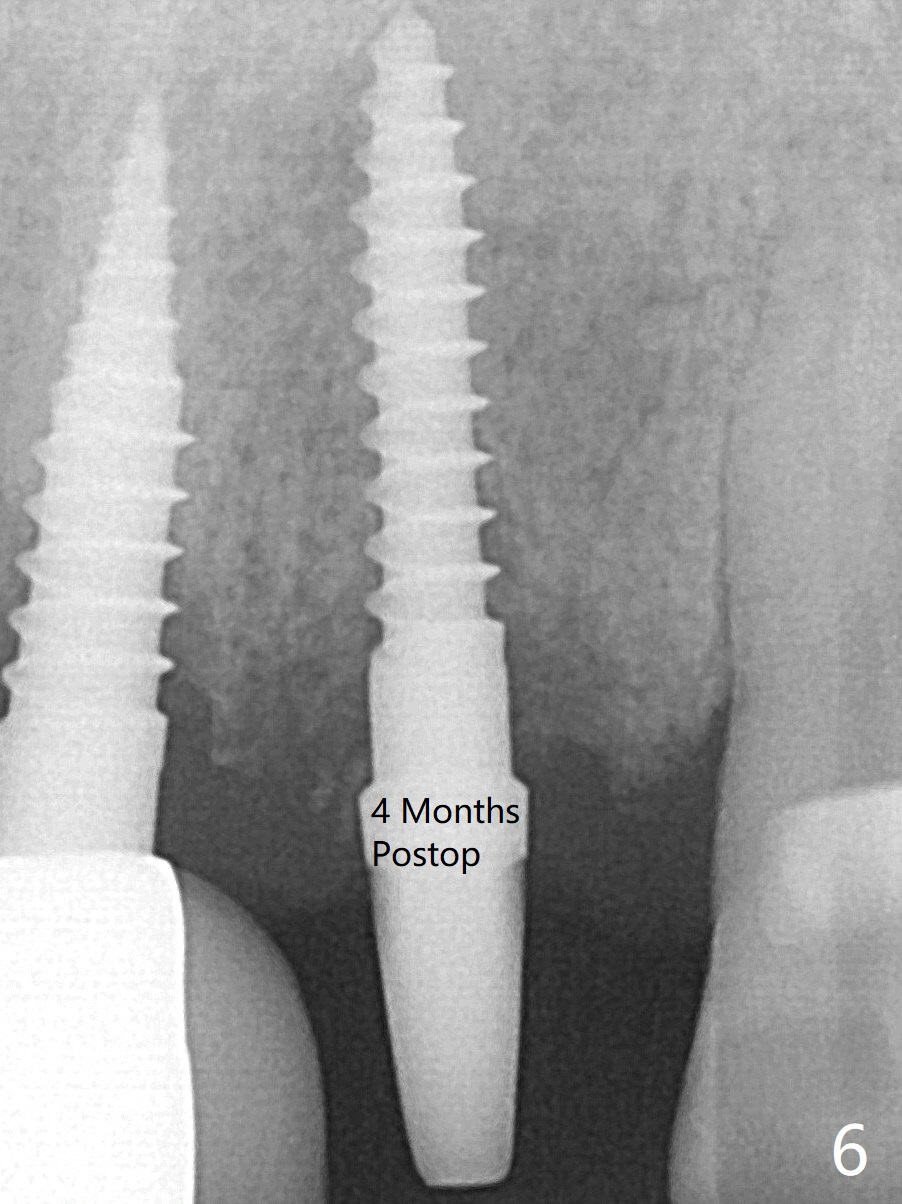

Following trajectory confirmation (Fig.2), a 2.5x12(2) mm implant is placed a little deeper than expected to ensure no implant thread exposure with bone graft (Fig.3).  The threads appears to be covered by the bone or bone graft 4 months postop (Fig.6).